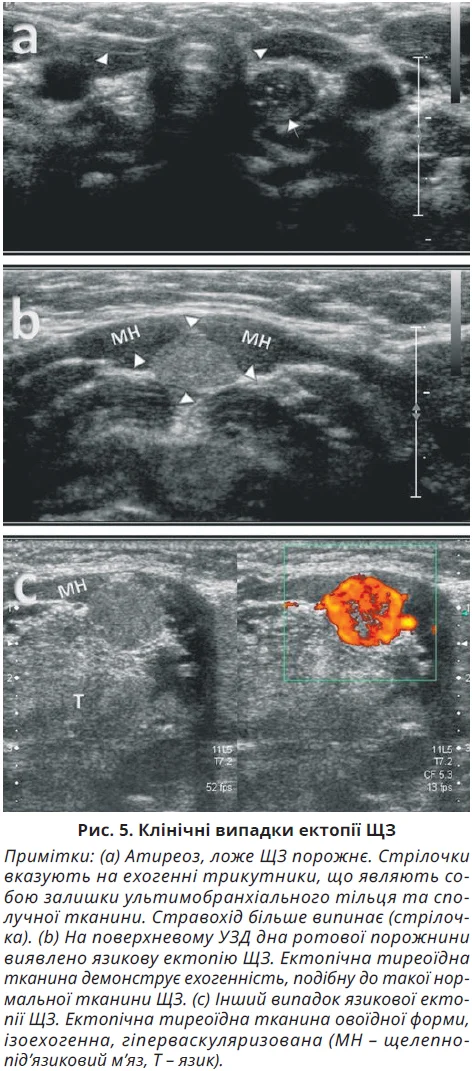

Атиреоз – це наявність порожнини в щитоподібному ложі, спричинена агенезією або ектопією ЩЗ. При атиреозі наявність ехогенних трикутників (зазвичай менших за 5 мм) по обидва боки трахеї, що являють собою залишки ультимобранхіального тільця та сполучної тканини, може бути помилково інтерпретована як гіпопластична чи диспластична ЩЗ. Ці гіперехогенні тканини, що іноді містять мікрокісти, демонструють мінімальний або повністю відсутній кровоток на кольоровій доплерографії. Ультразвукова картина атиреозу, спричиненого агенезією ЩЗ, показана на рисунку 4.

Через особливості ембріології ЩЗ при виявленні в пацієнта атиреозу потрібне сканування шиї згідно з ембріологічним міграційним шляхом ЩЗ, від основи язика до верхнього середостіння по середній лінії. Ектопічна ЩЗ може перебувати в лінгвальному, сублінгвальному, гіоїдному, інфрагіоїдному та середостінному положеннях. Лінгвальна ЩЗ є найпоширенішою формою ектопії ЩЗ та виявляється в 75% пацієнтів із функціональними тиреоїдними тканинами в разі вродженого гіпотиреозу. На УЗД-знімках ектопічна тиреоїдна тканина має чітко окреслену овальну форму, а на кольоровій доплерограмі вона зазвичай гіперваскулярна. У неонатальному періоді ектопія може не проявлятися завдяки достатньому виробленню тиреоїдних гормонів, тоді як у ранньому дитинстві через зростання потреби в гормонах ЩЗ може проявитися гіпотиреоз. Виявлення ектопічної ЩЗ при сцинтиграфії залежить від розміру та функціональної активності залози. Ретростернальні, ендоларингеальні або ендотрахеальні ектопічні ЩЗ у середостінні зазвичай не виявляються сонографічно, в цьому випадку потрібне сцинтиграфічне дослідження. Клінічні випадки язикових ектопічних утворень ЩЗ представлено на рисунку 5.